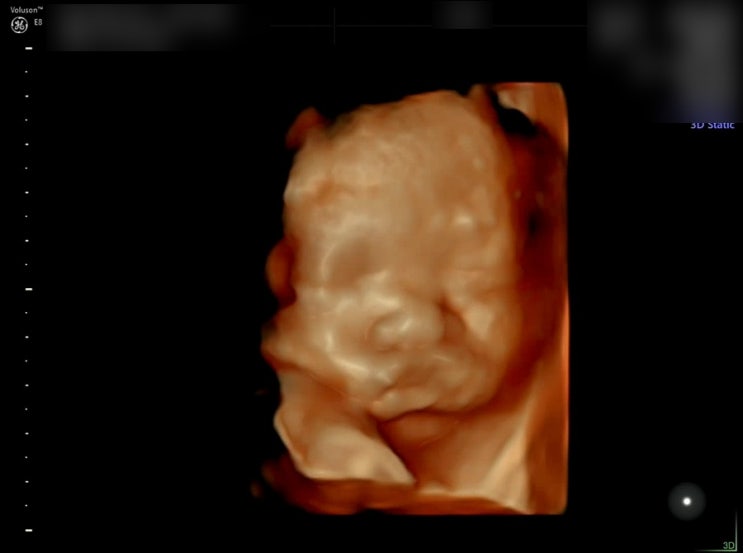

D-113 우리 행복이와 함께한 지 벌써 6개월! 내일이면 24주차 ❤︎ 걱정쟁이 엄마와 달리 항상 잘 커주고 ...